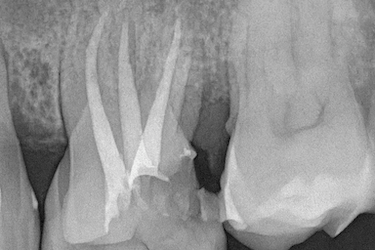

Antes de realizar una endodoncia dental, el odontólogo evalúa el estado del diente y la encía para detectar caries profundas, fracturas o infecciones que afecten al nervio.

Se realizan pruebas de sensibilidad y una radiografía periapical o panorámica para confirmar si existe daño pulpar o inflamación en la raíz. Estas imágenes ayudan a planificar el tratamiento de conducto con precisión.

Si la estructura del diente puede conservarse, la endodoncia permite eliminar la infección y mantener la pieza natural, evitando la extracción dental y la colocación posterior de un implante.

Si es necesario realizar una endodoncia, cuanto antes se lleve a cabo, mejor será el pronóstico del diente afectado. Conocido también como tratamiento de conducto o desvitalización del nervio, se realiza en aquellos casos en los que la pulpa dental se ha dañado por una caries profunda, un golpe o una infección.

Cuando una fractura alcanza la pulpa dental, el nervio queda expuesto y puede inflamarse o infectarse.

En estos casos, la endodoncia permite conservar la pieza y eliminar el dolor.

Cuando la infección en un diente se expande dentro del hueso, se produce una inflamación que provoca una sensación de movilidad del diente y dolor en la muela o diente.

El paciente puede presentar ganglios inflamados y hasta fiebre. El tratamiento de endodoncia es necesario cuando la cavidad o hueco del diente es muy profunda y llega al nervio.